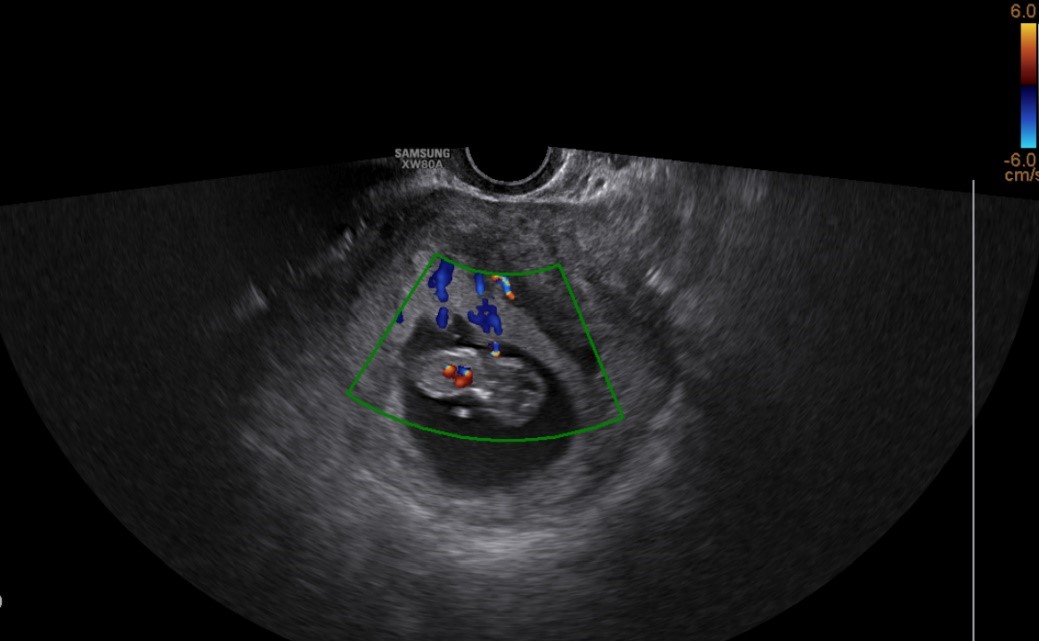

试管婴儿的B超图片